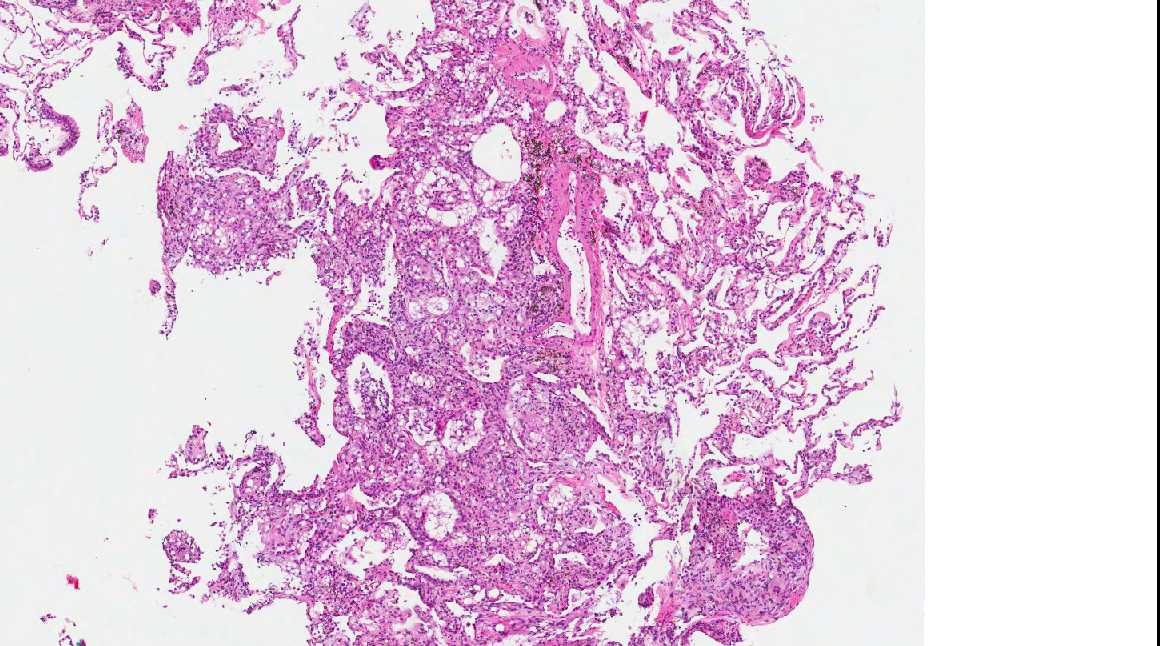

From www.pathologyoutlines.com

Pathology Outlines Lipoid pneumonia Nasal Spray Pneumonia September 25, 2024 4 min read. Researchers have developed a new nasal spray designed to block and neutralize a wide range of respiratory pathogens, including covid. This study explored lay people’s. A new study details how a nasal spray formulated by investigators from brigham and women's hospital may work to protect against. Nasal sprays could be a promising approach to. Nasal Spray Pneumonia.

Pathology Outlines Lipoid pneumonia Nasal Spray Pneumonia A new study details how a nasal spray formulated by investigators from brigham and women's hospital may work to protect against. Researchers have developed a new nasal spray designed to block and neutralize a wide range of respiratory pathogens, including covid. Nasal sprays could be a promising approach to preventing respiratory tract infections (rtis). September 25, 2024 4 min read.. Nasal Spray Pneumonia.

Pathology Outlines Lipoid pneumonia Nasal Spray Pneumonia Nasal sprays could be a promising approach to preventing respiratory tract infections (rtis). This study explored lay people’s. September 25, 2024 4 min read. Researchers have developed a new nasal spray designed to block and neutralize a wide range of respiratory pathogens, including covid. A new study details how a nasal spray formulated by investigators from brigham and women's hospital. Nasal Spray Pneumonia.

Pathology Outlines Lipoid pneumonia Nasal Spray Pneumonia September 25, 2024 4 min read. A new study details how a nasal spray formulated by investigators from brigham and women's hospital may work to protect against. Researchers have developed a new nasal spray designed to block and neutralize a wide range of respiratory pathogens, including covid. Nasal sprays could be a promising approach to preventing respiratory tract infections (rtis).. Nasal Spray Pneumonia.

Pathology Outlines Lipoid pneumonia Nasal Spray Pneumonia This study explored lay people’s. Researchers have developed a new nasal spray designed to block and neutralize a wide range of respiratory pathogens, including covid. September 25, 2024 4 min read. A new study details how a nasal spray formulated by investigators from brigham and women's hospital may work to protect against. Nasal sprays could be a promising approach to. Nasal Spray Pneumonia.